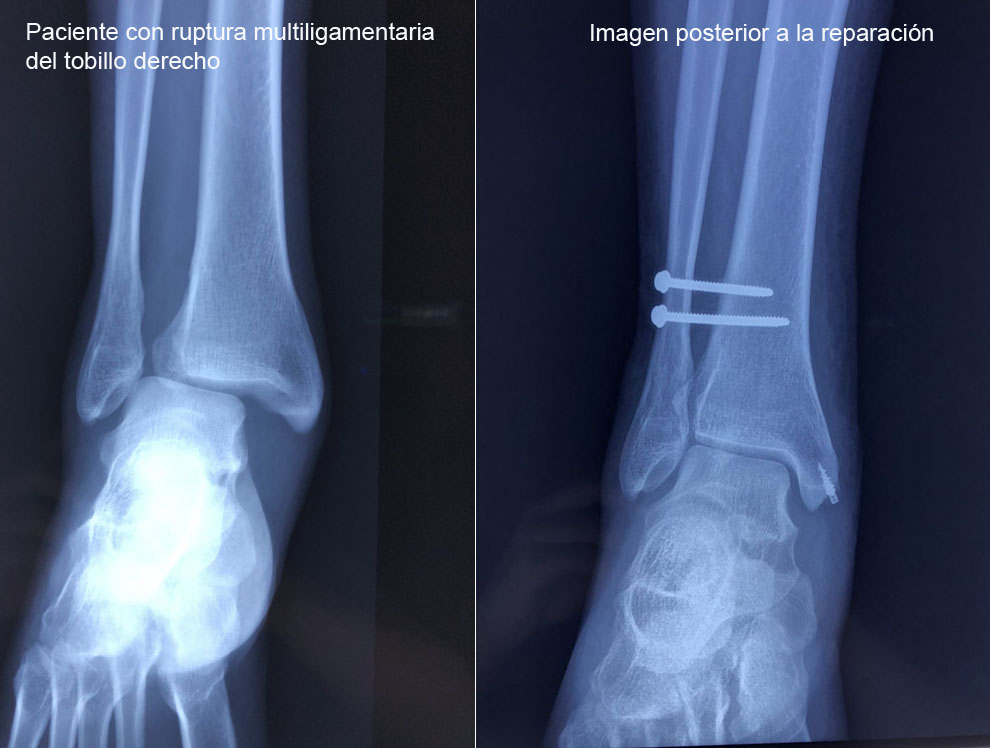

Los esguinces son lesiones ligamentarias que pueden variar en diversos grados de severidad, los cuales pueden ser desde una simple distensión de las fibras hasta una rotura total de las mismas. Por lo que es indispensable una adecuada valoración y un tratamiento oportuno para evitar las complicaciones.

Es el ligamento que con mayor frecuencia se lesiona cuando presentamos la inversión forzada del tobillo, este se encuentra en el borde anterior del maléalo lateral hasta la región adyacente del astrágalo.

El ligamento deltoideo es el principal estabilizador medial del tobillo, evita que el tobillo se vaya en eversión. El ligamento está formado por dos capas. Su ruptura condiciona inestabilidad medial del tobillo.